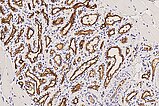

In the 250× detail magnification of GLUT1 staining, infantile hemangioma capillaries exhibit characteristic immunohistochemical GLUT1 expression (brown staining of the endothelial cell layer), which normally shows positivity only in placental capillaries and vascular tumors derived from them. Hence, the assumption that infantile hemangiomas are derived from vascular precursor cells of the placenta. In other hemangiomas (e.g., congenital hemangiomas such as NICH or RICH), GLUT1 is negative. This is the most important differential diagnostic histological criterion for infantile hemangioma. The erythrocytes contained in the lumina also show GLUT1 positivity and thus serve as a positive internal control that the staining has worked well technically.